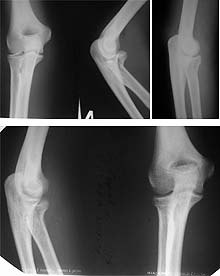

Уважаемые коллеги. Индивидуальное решение проблемы-однозначно. Как ни страноо, хорошие результаты дает закрытая репозиция по методу Свинухова. Найти технологию можно у детских травматологов. Ждя взрослого сама методика выглядит немного дикой, но попробуйте-не пожалеете!

В качестве примера, 4 дня после травамы, в стационарах города обсуждается вопрос-ничего не денлать, удалить, эндопротезирование. Закрытая репозиция, результат через 6 недель.